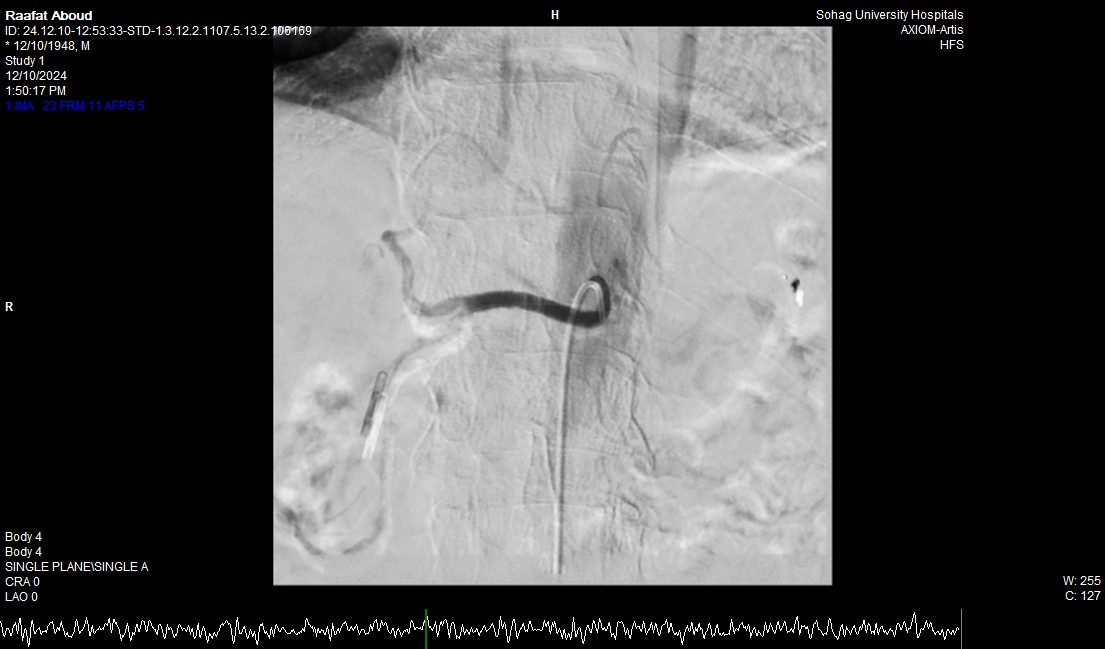

وأضاف الدكتور أحمد كمال المدير التنفيذي للمستشفيات الجامعية جامعة سوهاج، أنه بعد إجراء الفحوصات للمريض تبين وجود قرحة كبيرة بالإثنى عشر وشريان نازف، حيث نجح الفريق في التحكم المبدئي بالنزيف عن طريق تركيب مشبك معدني بالمنظار وحقن للقرحة النازفة، ثم تم استدعاء فريق أطباء وحدة الأشعة التداخلية على الفور وتم عمل غلق للشريان النازف بشكل عاجل من خلال جهاز القسطرة.

وأوضح الدكتور محمد زاكي رئيس قسم الأشعة، أن مثل هذه الحالات تعد من الطوارئ الطبية الخطيرة والتي تستوجب عمل قسطرة شريانية عاجلة لغلق الشرايين النازفه، مشيرًا أن وحدة الأشعة التداخلية تم تزويدها بجهاز أشعة محوري متقدم لاجراء مثل هذه الحالات، وأن هذا النجاح هو نتيجة لتعاون أقسام المستشفى مع وحدة الأشعة التداخلية لتقديم خدمة مميزة للمرضى.